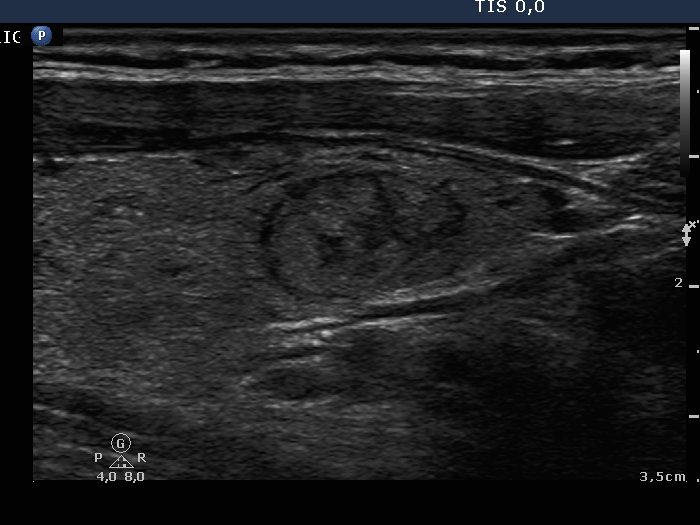

Intact right lobe without any pathological finding and benign hyperplastic nodules in the left lobe (histological diagnosis) - case 803

Right lobe

Left lobe

Both the pseudonodule in the right lobe (upper images) and the benign nodule in the left lobe (lower images) have numerous pale granules and lines which correspond to the normal architecture of the thyroid and correspond to a connective tissue. The finding of a few more bright granules and lines are the ultrasound presentation of a thickened connective tissue.